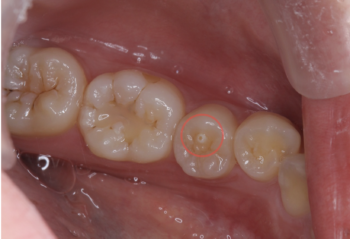

中心結節(ちゅうしんけっせつ)とは、小学校高学年頃に生えてくる大人の歯(永久歯)のうち、特に下顎の第一小臼歯や第二小臼歯に見られる小さな突起状の構造です。発生率はおよそ数%といわれており、決して珍しいものではありません。

この突起は、歯の表面の真ん中やや内側に現れることが多く、外見上は「小さなツノ」や「こぶ」のように見えることもあります。

一見、単なる形の違いのように思われますが、中心結節の内部には歯の神経が通っている場合があるため、そこが折れてしまうと大きなトラブルにつながることがあります。